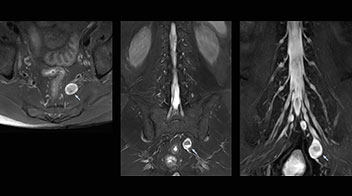

Implementing NerveVIEW without lengthening exam time “The source images of NerveVIEW exhibit a contrast similar to STIR or fat-suppressed T2-weighted images. So, in our neurography exams we are replacing the 2D T2-weighted coronal sequence with 3D NerveVIEW. With this, we add a lot of useful information without adding scan time. This is important for patients with severe lower extremity symptoms, as they often find it difficult to maintain still during the whole MRI examination, so the exam should be as short as possible.” “We have currently implemented 3D NerveVIEW on our Achieva 3.0T dStream MRI system only. Because the 3D NerveVIEW method is based on a background signal suppression technique, we decided to use the high SNR of our 3.0T MRI system for obtaining the best possible visualization of peripheral nerves,” says Tanji. “Where NerveVIEW of the lumbar plexus is currently used as a subroutine scan for patients with strong lower limb symptoms, its use for visualization of the brachial plexus, is currently limited to special cases such as schwannomas and neuritis, usually only 1 or 2 cases per month.”

Lumbar spine MRI

examination with 3D NerveVIEW

T1W sagittal and axial

3D NerveVIEW

T2W sagittal and axial